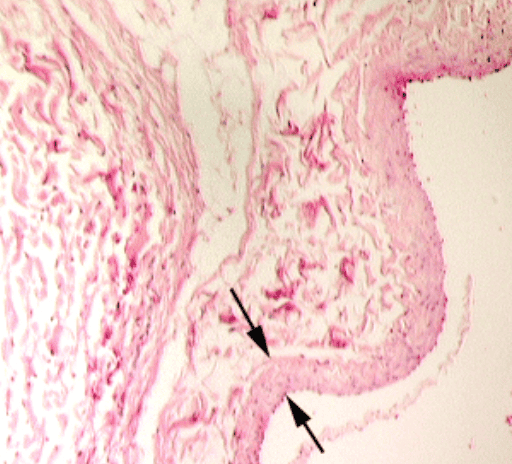

Thyroid Gland

Thyroid Gland